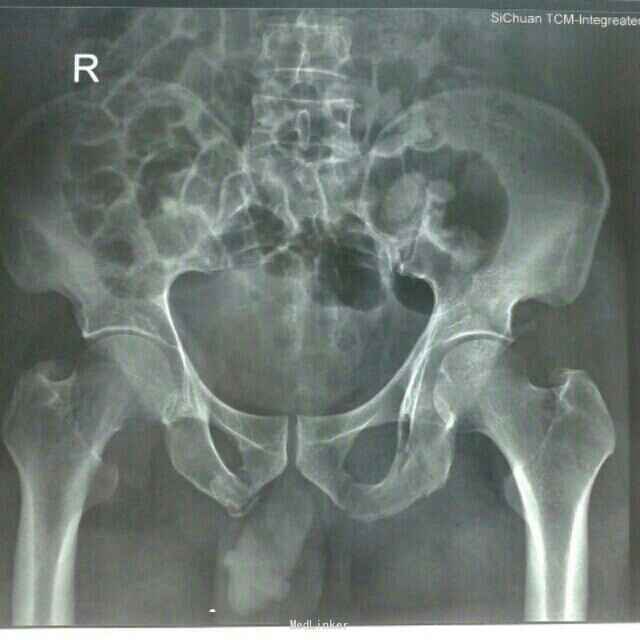

诊断:1、重物挤压伤 2、左髋臼骨折合并髋关节后脱位 3、骨盆粉碎性骨折 4、左股骨头骨折 治疗:患者入院后,予以完善术前检查,药物消肿、止痛、止血、补充血容量、保护胃粘膜及预防血栓形成等对症支持治疗,急诊在局部麻醉下行了“左髋关节脱位手法整复+左股骨髁上骨牵引”术,纠正髋关节后脱位及骨折错位畸形, 减轻髋关节压力,降低股骨头坏死的发生几率;经牵引治疗1周后,患者左髋关节弹性固定畸形及左下肢内旋、内收畸形纠正;复查牵引后DR及CT回示:左髋关节脱位已经纠正,骨折错位明显改善,完善相关检查及术前准备在"全身麻醉"下行了"骨盆粉碎性骨折切开复位钢板螺丝钉内固定+同种异体骨植骨+左胫骨结节骨牵引术"。术中见:左侧髋臼顶部及后侧壁骨折,呈粉碎性,后侧骨折线自髋臼上缘3.0cm处向后下走形,连接左侧坐骨支,向外后移位改变,左股骨头向后上脱位不稳,左侧髋臼顶部骨块向外上翻转移位,左髋臼内顶及后壁及股骨头见部分软骨挫伤、凹陷、瘀血,关节腔内见多枚细小骨碎片,关节腔及骨折断端见部分关节囊及软组织嵌顿。术后予患肢继续左下肢胫骨结节骨牵引制动,结合药物静滴预防感染、消肿、止痛、止血、改善血循环等处理,并指导患者行患肢主动功能锻炼;术后2周伤口愈合拆线,住院40天好转出院。